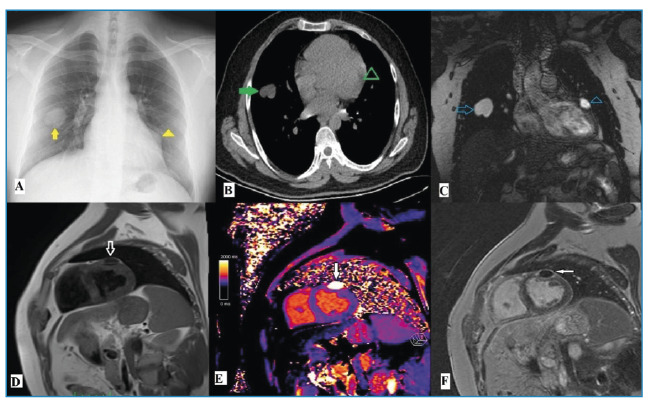

Incidentally Detected Cardiac Hydatid Cyst: A Rare Case Report.